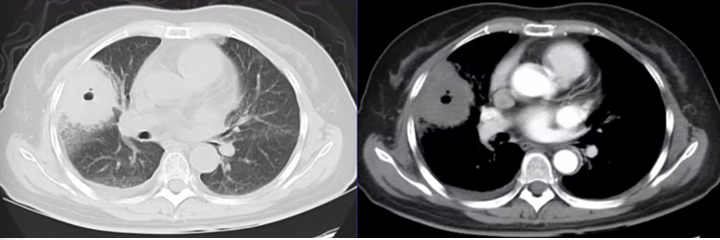

曲霉感染出现的晕征是曲霉侵犯血管导致血管破裂,红细胞向外渗出,其在肺部弥散受到一定限制,因此在正常肺与晕征之间可以勾画出一个大致的轮廓,边界清晰。细菌感染出现的磨玻璃影的实质是水肿,因为细菌感染导致血管扩张,血管的通透性增加,血液中的液体向外渗出,所以这种磨玻璃影的构成成分是水,水在肺组织中弥散,使二者之间的分界不清(图14)。因此,在临床中应注意区分这两种影像。

图片

图14  细菌感染与曲霉感染所致“晕征”的区别

注:左图为细菌感染出现的磨玻璃影,右图为曲霉感染出现的晕征。